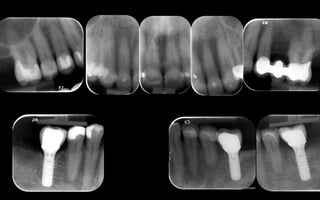

radiographic examination